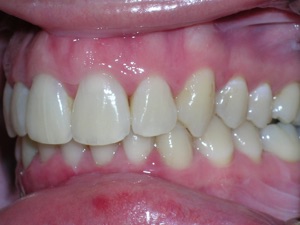

Now for the final results.

Needless to say, we were both quite happy with the outcome. Using elastics we were able to push back the back teeth and create space for the two teeth stuck behind.